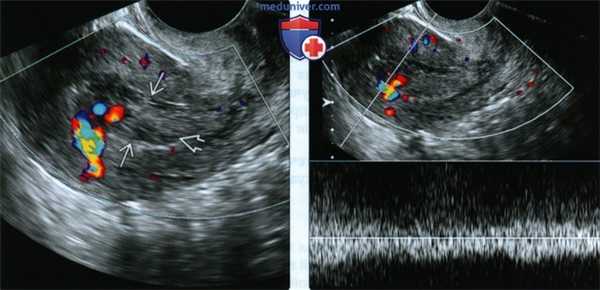

(Слева) Трансвагинальное ЦДК, продольное сканирование. Пациентка после самопроизвольного аборта в I триместре. В полости матки определяются сложные гиперэхогенные сосудистые образования. Также отмечаются небольшие кистозные очаги, характерные для ЗПЗ после самопроизвольного аборта.

(Справа) Тот же случай. Импульсная допплерография. Визуализируется хаотичный артериальный и венозный кровоток, напоминающий картину артериовенозной мальформации. После эвакуации остатков плодного яйца данный кровоток исчезает.